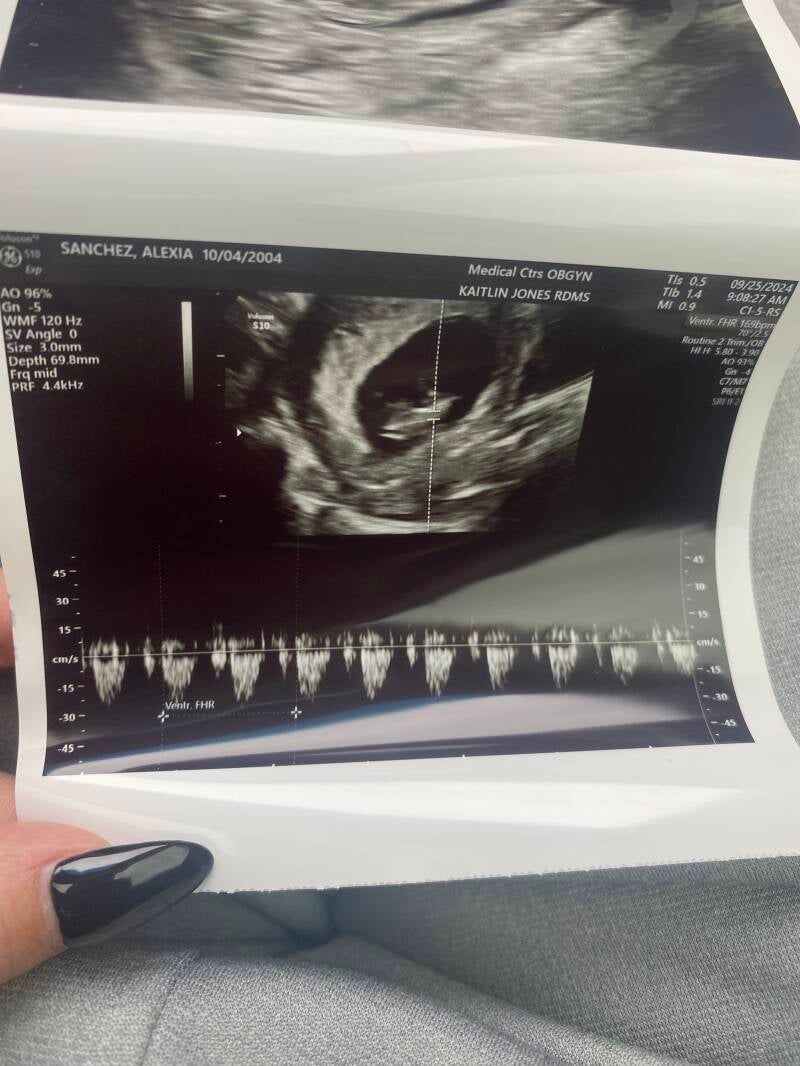

My first doctor's appointment was on September 25, 2024—a moment that truly made everything feel real. We were going to have a baby! The thought of my body nurturing a tiny human, whose life would soon be in our hands, was both overwhelming and exhilarating. I felt an incredible mix of joy and nerves all at once. Seeing her for the first time was absolutely heartwarming. These ultrasound images were taken at 11 weeks and 1 day, and her heartbeat was so strong—169 beats per minute! Everything went perfectly, and it was such a beautiful experience.